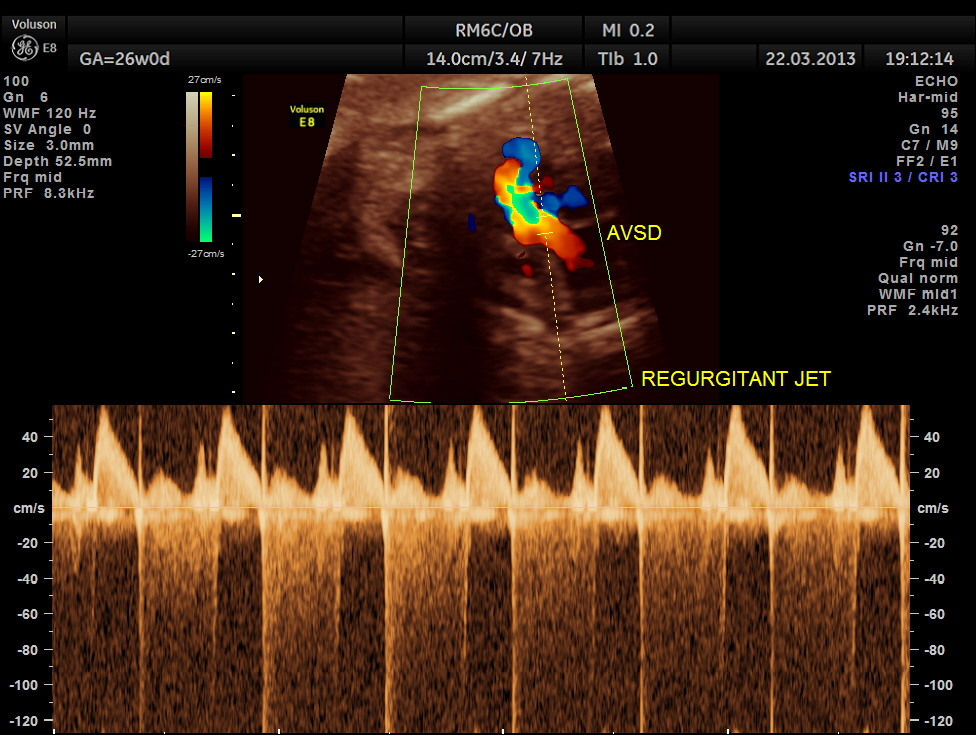

STIC image shows ATRIO VENTRICULAR SEPTAL DEFECT ( ENDOCARDIAL CUSHION DEFECT )

The next image shows spectral doppler showing prominent regurgitant jet in A V SEPTAL DEFECT

To summarise this fetus had

4. Prominent regurgitant jet seen at A V septal defect